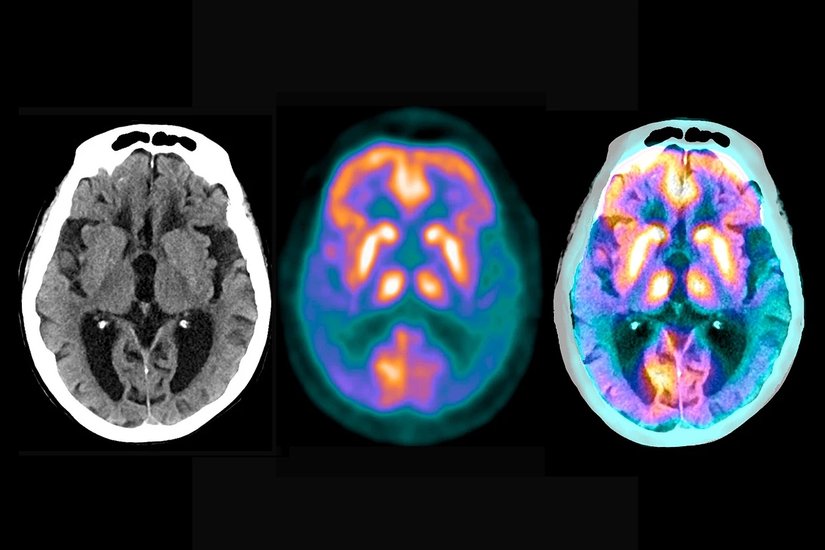

Biogen ve Eisai biyoteknoloji şirketleri tarafından tıpkı ilk filmdeki gibi Alzheimer tedavisi için geliştirilen bir gen terapisi yöntemi olan Lecanemab (Leqembi), beyindeki beta-amiloidi hedef alan ve ortadan kaldıran bir antikor intravenöz infüzyon tedavisidir. Beta amiloid, Alzheimer hastalığında bulunan beyin lezyonlarından biridir. Alzheimer hastalığındaki zihinsel bozukluklara sebep olan temel faktör, beyindeki anormal beta amiloid plakları ve tau proteinlerinin birikmesidir. Bu plaklar ve proteinler, sinir hücreleri arasındaki iletişimi engelleyerek sinir hücrelerinin ölümüne neden olabilir. Bu süreç, özellikle hipokampüs gibi hafıza ve bilişsel işlevlerden sorumlu bölgelerde önemli hasara yol açar. Ayrıca, Alzheimer hastalığı beyindeki diğer alanlarda da genişleyebilir, bu da genel zihinsel bozukluklara ve demansa yol açabilir.[7]

Hafif bilişsel bozukluk (MCI) veya Alzheimer hastalığına bağlı hafif demansla yaşayan kişiler de dahil olmak üzere Alzheimer hastalığının erken tedavisi için FDA'dan onay almıştır. Lecanemab, beyindeki beta-amiloidi düşürür ve erken dönem Alzheimer hastalığıyla yaşayan kişilerde bilişsel ve işlevsel gerilemeyi azaltır.

Fakat bu tedavi de beraberinde birtakım yan etkiler getirebilir. Bu sınıftaki ilaçlarda diğer anti-amiloid tedavileri gibi lecanemabın da yan etkileri vardır. Lecanemab ciddi alerjik reaksiyonlara neden olabilir. En sık bildirilen yan etkiler infüzyonla ilişkili reaksiyonlar, amiloidle ilişkili görüntüleme anormallikleri (ARIA) ve baş ağrısıdır.